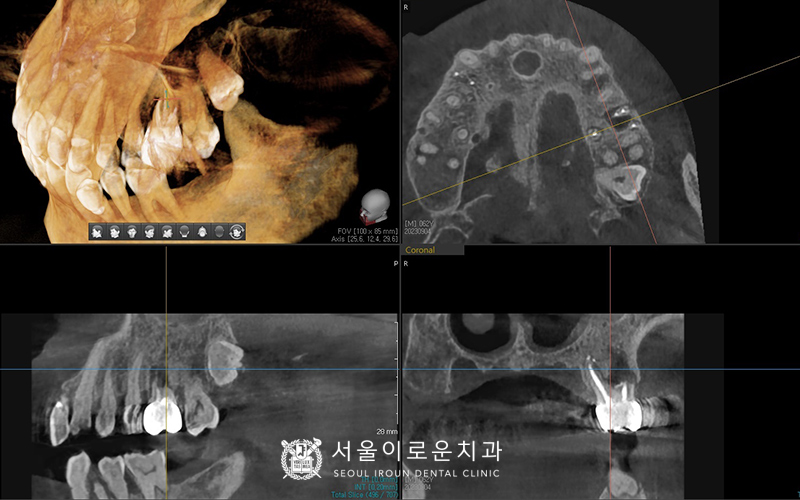

수술에 앞서, CT 촬영을 시행하였습니다.

환.자분의 경우, 아래의 상태로

더욱 꼼꼼한 체크가 필요하였습니다.

1) 60대라는 점

2) 고혈압을 갖고 계신다는 점

3) 잦은 흡연을 하신다는 점